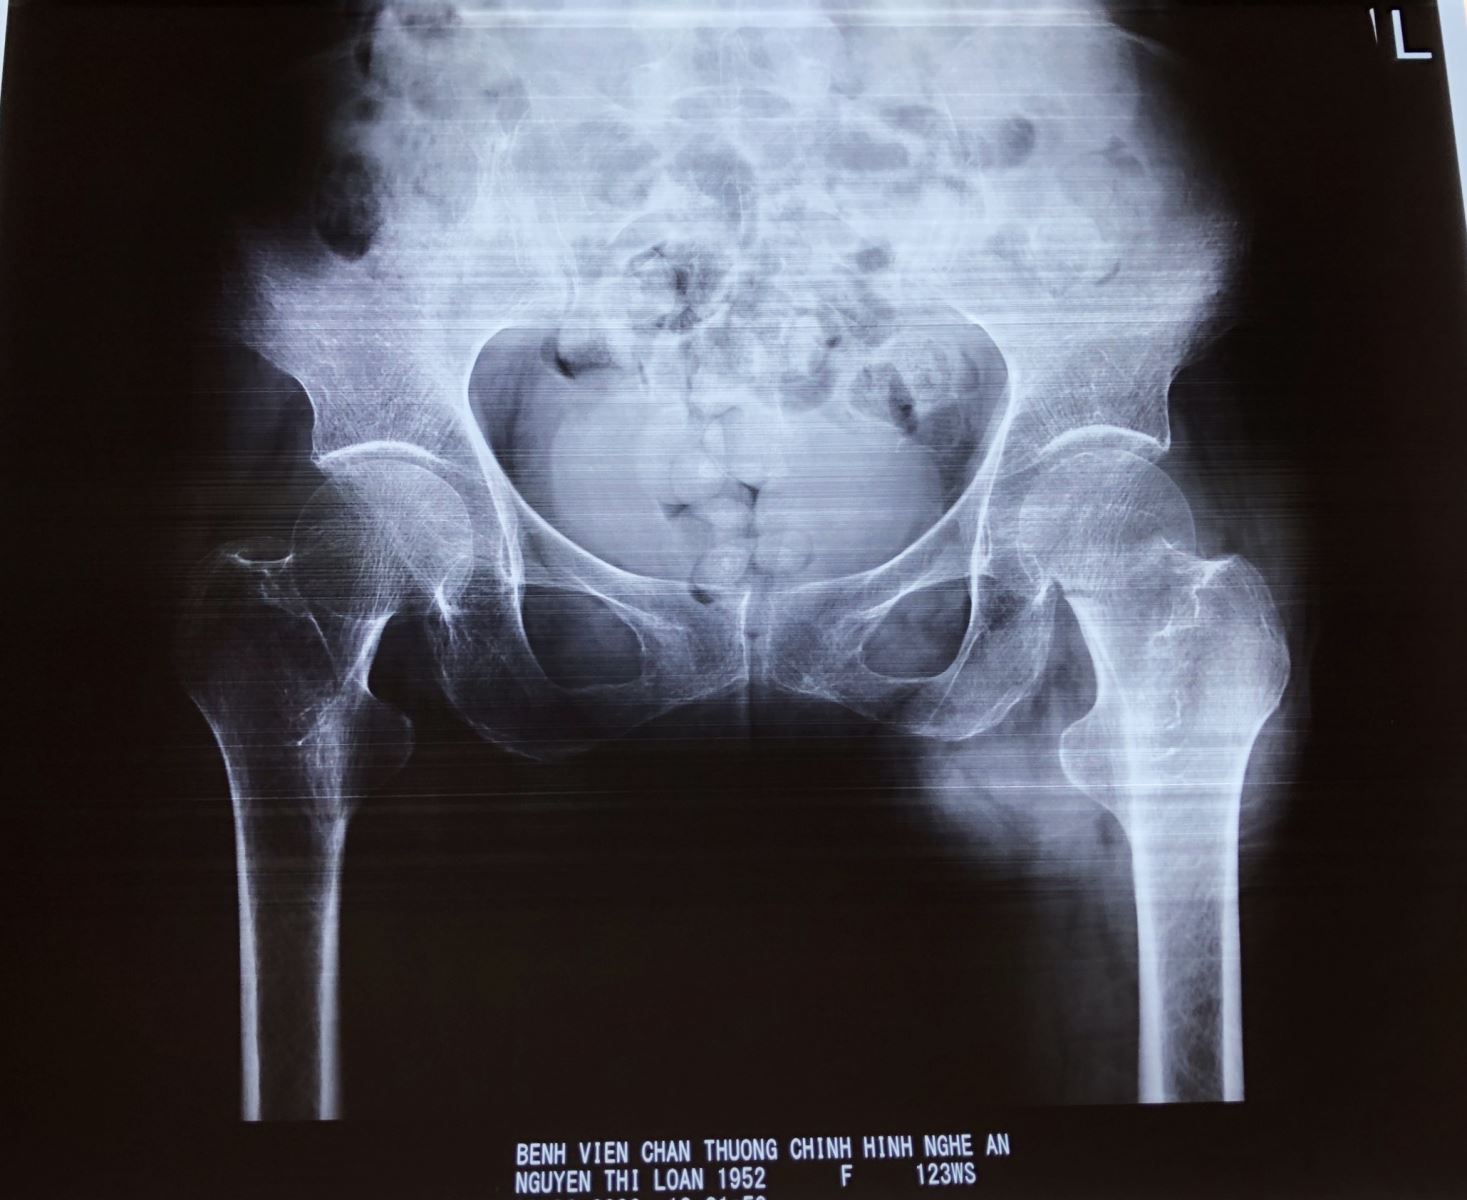

• Chẩn đoán xác định bằng chụp phim xquang khung chậu và khớp háng bên nghi ngờ gãy cổ xương đùi.